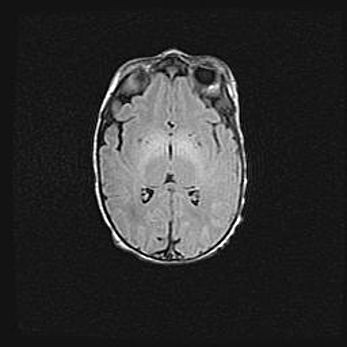

Открытая гидроцефалия.

Возраст: 9 месяцев 12 дней

Вес: 6800 г

Пол: мужской

Окружность головы: 41,5 см

Срок гестации: 28 недель

Гидроцефалия головного мозга у новорожденных имеет характерный признак: опережающий рост окружности головы приводит к визуально хорошо определяемой гидроцефальной форме сильно увеличенного в объёме черепа. Детские неврологи определяют следующие симптомы гидроцефалии у грудничков: выбухающий напряжённый родничок, частое запрокидывание головы, смещение глазных яблок к низу.